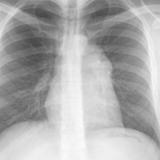

Case 8a Thymoma PA

Date: 03/27/2009

Views: 9543